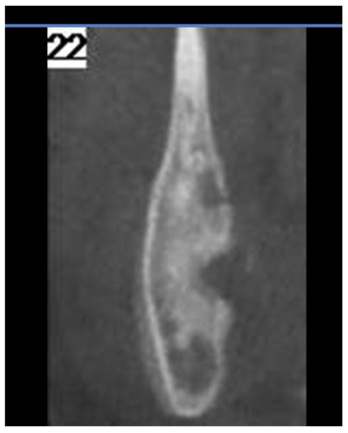

Dopo circa 2 mesi di remissione C. ha ricominciato a presentare saltuario dolore alla caviglia sinistra, con incostante limitazione funzionale, per cui ha ricorso alla terapia antinfiammatoria al bisogno. Inoltre da alcuni mesi ricomparsa di dolore e tumefazione in sede mandibolare destra. Al controllo, per il persistere della sintomatologia, si decide di ripetere la RMN del massiccio facciale che conferma l�interessamento del massetere ed evidenzia un possibile coinvolgimento osseo (Figura 1). C. ha cos� eseguito una TC che ha mostrato un disomogeneo addensamento della trama ossea in corrispondenza della branca montante e dell�angolo mandibolare di destra con qualche areola con aspetto erosivo superficiale del profilo dell�osso, in parte sfumato (Figure 2 e 3). Gli aspetti clinico e radiologico hanno deposto per un quadro di tipo infiammatorio da osteomielite cronica asettica.

Figura 2. TC.

Figura 3. TC.